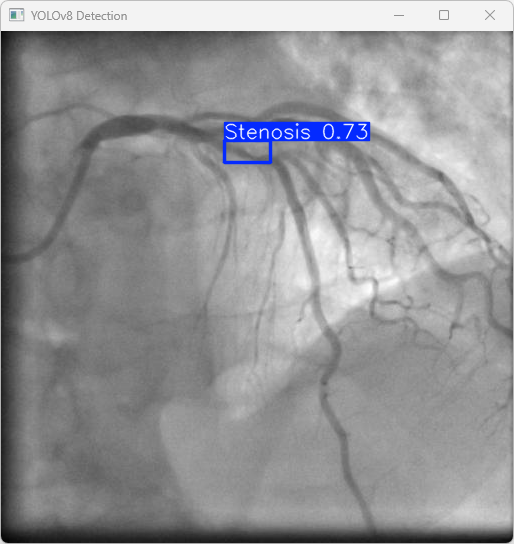

执行imgTest.py代码后,会将执行的结果直接标注在图片上,结果如下:

这段输出是基于YOLOv8模型对图片“imagetest.jpg”进行检测的结果,具体内容如下:

图像信息:

(1)处理的图像路径为:TestFiles/imagetest.jpg。

(2)图像尺寸为640×640像素。

检测结果:

(1)模型在图片中检测到:1 个Stenosis(狭窄性血管病变)。

处理速度:

(1)预处理时间: 5.0 毫秒

(2)推理时间: 6.2 毫秒

(3)后处理时间: 98.6毫秒

总结:

YOLOv8模型成功检测出1个狭窄性血管目标,推理速度高效,结果保存在指定目录,可进一步优化后处理速度和泛化性能。